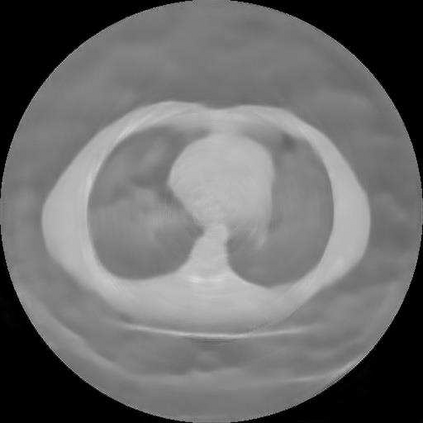

Sparse-view computed tomography (CT) is known as a widely used approach to reduce radiation dose while accelerating imaging through lowered projection views and correlated calculations. However, its severe imaging noise and streaking artifacts turn out to be a major issue in the low dose protocol. In this paper, we propose a dual-domain deep learning-based method that breaks through the limitations of currently prevailing algorithms that merely process single image slices. Since the scanned object usually contains a high degree of spatial continuity, the obtained consecutive imaging slices embody rich information that is largely unexplored. Therefore, we establish a cascade model named LS-AAE which aims to tackle the above problem. In addition, in order to adapt to the social trend of lightweight medical care, our model adopts the inverted residual with linear bottleneck in the module design to make it mobile and lightweight (reduce model parameters to one-eighth of its original) without sacrificing its performance. In our experiments, sparse sampling is conducted at intervals of 4{\deg}, 8{\deg} and 16{\deg}, which appears to be a challenging sparsity that few scholars have attempted before. Nevertheless, our method still exhibits its robustness and achieves the state-of-the-art performance by reaching the PSNR of 40.305 and the SSIM of 0.948, while ensuring high model mobility. Particularly, it still exceeds other current methods when the sampling rate is one-fourth of them, thereby demonstrating its remarkable superiority.